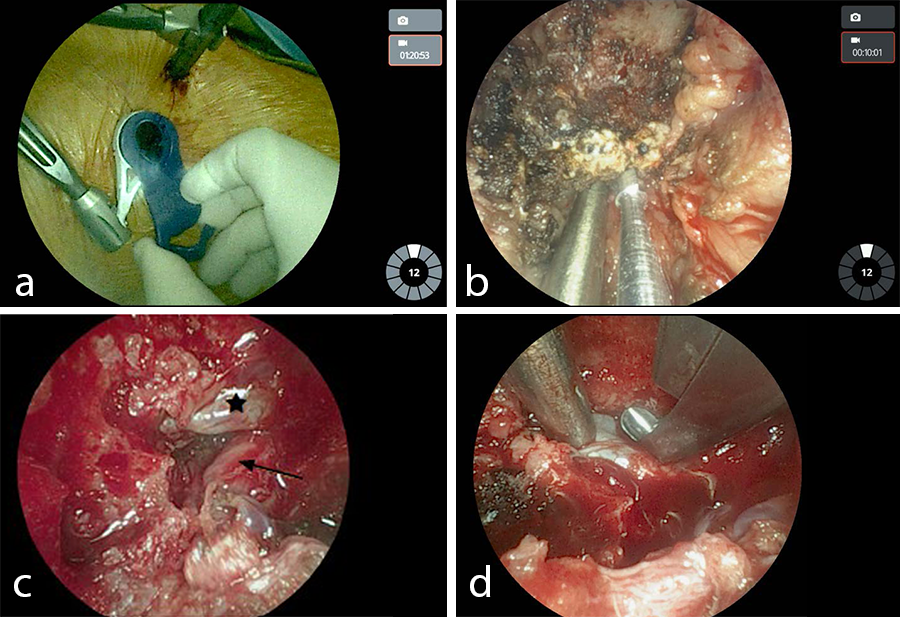

- Left L4/L5 VueLIF™ Procedure utilizing the TELIGEN™ System

- Patient-mounted TELIGEN™ tubular access system using a MIS-TLIF approach (Fig 9)

- Discectomy with TELIGEN™ Clear